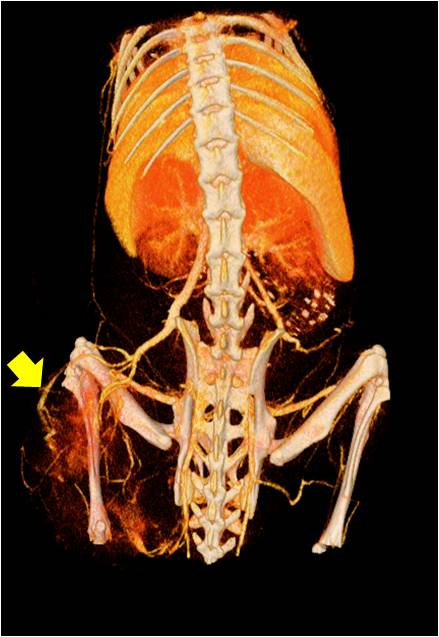

腫瘤血管生成

心血管

胸部和心血管的層析成像 胸部和心血管的3D圖像